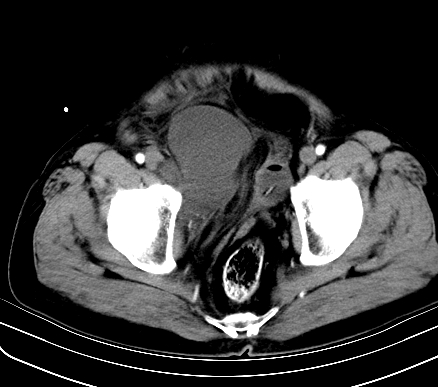

标题: CT19729B:男,74岁,因腿疼就诊,查体触腹部肿物,

增强扫描

静脉期

【ct表现】

1、肿块巨大,往往位于腹膜后,长大后才引起症状而就诊;那么位于腹膜后的肿瘤80%为恶性肿瘤。

2、实性肿瘤,增强扫描轻度不均强化,实性肿瘤一般不是好东西。

3、肿瘤边缘似见少许脂肪样密度。

4、腹膜后未见肿大淋巴结,但肿瘤于临近的肠管及组织接触紧密。

【诊断】

腹部占位,考虑位于腹膜后的恶性肿瘤,脂肪肉瘤(实体型)可能性大。

术后病理结果:腹膜后脂肪肉瘤。